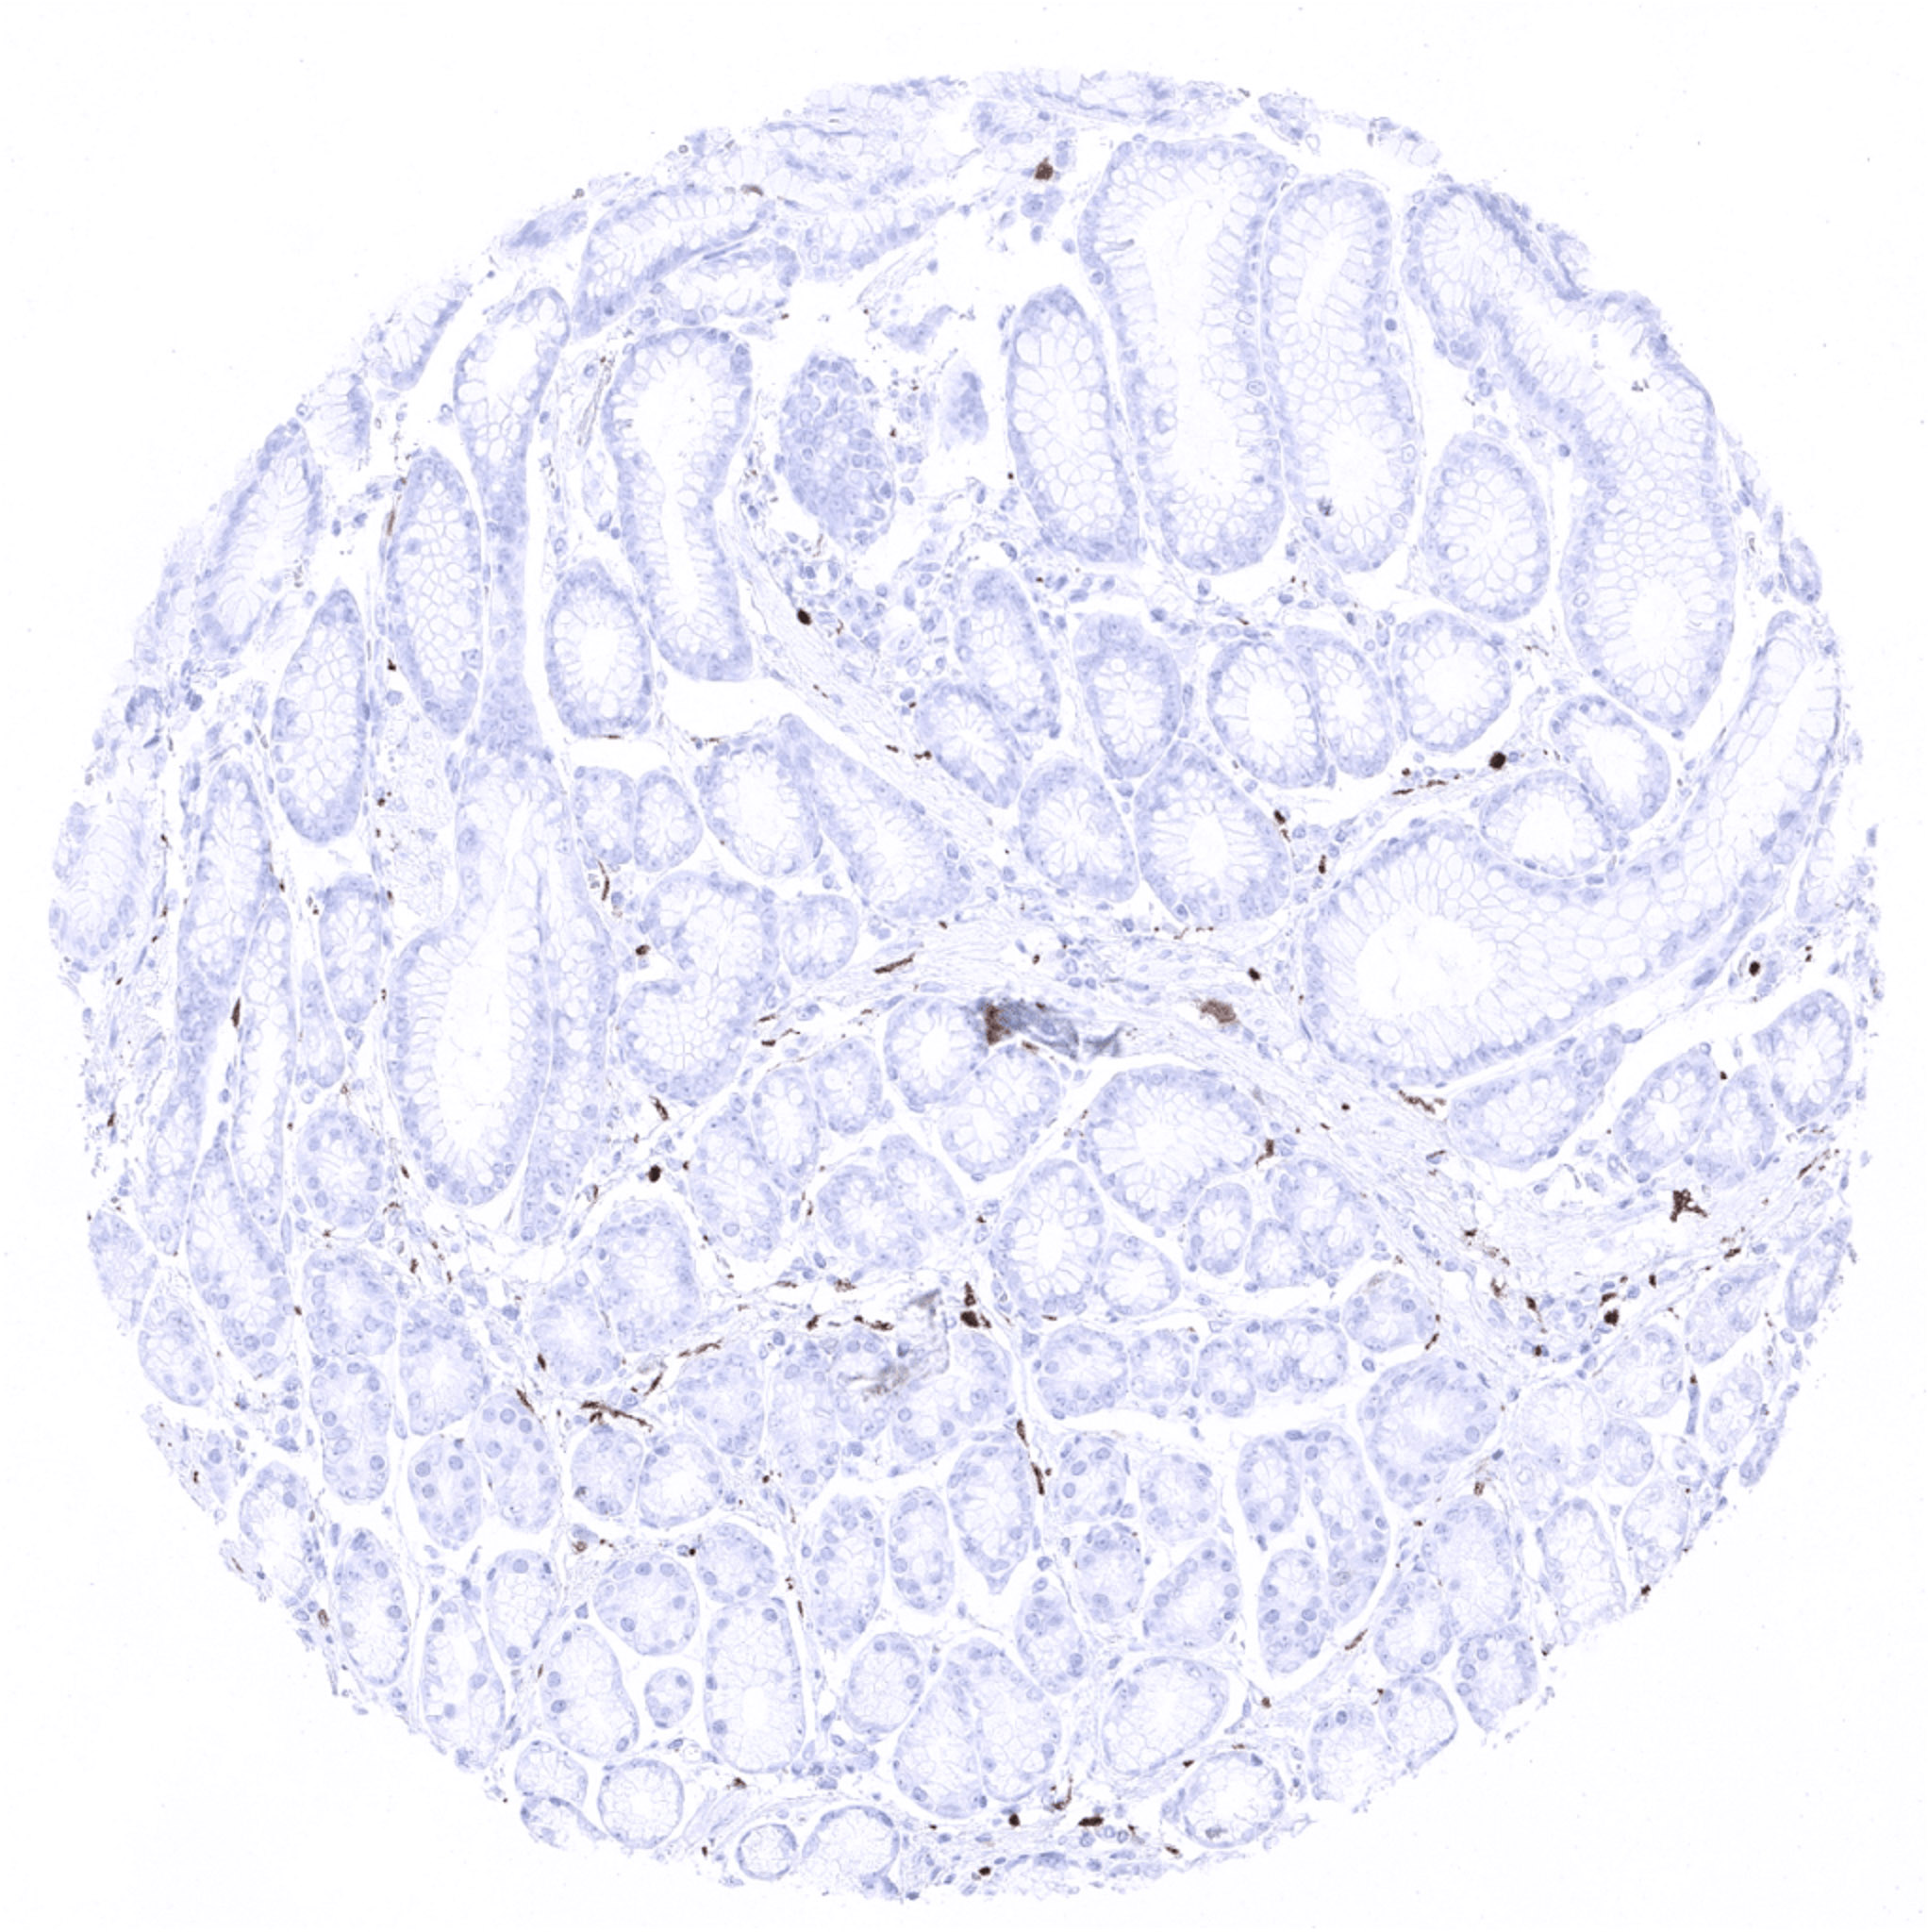

Colon descendens, mucosa

Colon descendens, muscular wall – Nerve fibres and ganglion cells are S100 beta positive.

Rectum, mucosa